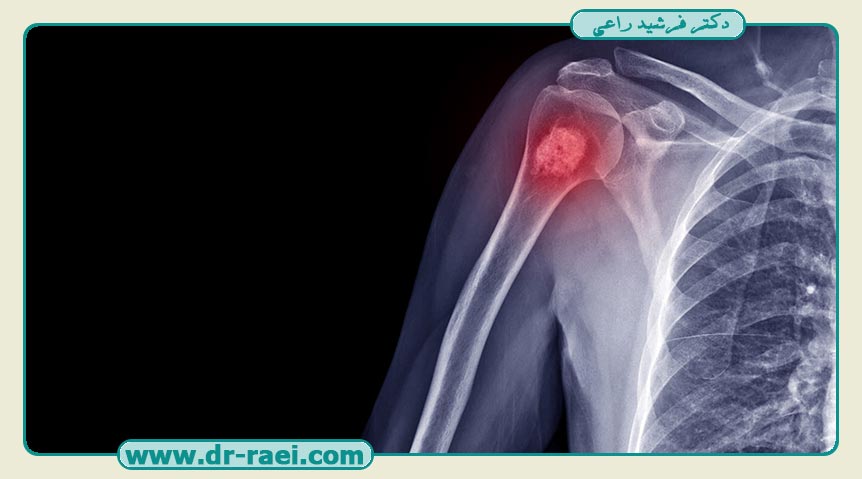

تومور استخوان چیست؟

هنگامی‌که سلول‌ها به‌طور غیرطبیعی و غیرقابل‌کنترل تقسیم می‌شوند، می‌توانند توده یا توده‌ای از بافت را تشکیل دهند. این توده تومور نامیده می‌شود. تومورهای استخوانی در استخوان‌های شما شکل می‌گیرند. با رشد تومور، بافت غیرطبیعی است که می‌تواند بافت سالم را جابجا کند. همواره تومورها می‌توانند به دودسته خوش‌خیم و بدخیم تقسیم شوند.

تومورهای خوش‌خیم سرطانی نیستند و معمولاً در جای خود باقی می‌مانند و بعید است که کشنده باشند، اما هنوز سلول‌های غیرطبیعی هستند و ممکن است نیاز به درمان داشته باشند. تومورهای خوش‌خیم می‌توانند رشد کنند و می‌توانند بافت استخوانی سالم شمارا فشرده کرده و باعث مشکلات بعدی شوند، اما تومورهای بدخیم سرطانی هستند و می‌توانند باعث گسترش سرطان در سراسر بدن شوند.

تست‌های تصویربرداری :پزشک احتمالاً برای تعیین اندازه و محل دقیق تومور، عکس‌برداری با اشعه ایکس را تجویز خواهد کرد که بسته به نتایج اشعه ایکس، آزمایش‌های تصویربرداری دیگر ممکن است ضروری و قابل انجام باشند. در ادامه به بررسی تعدادی از مهم‌ترین آزمایش‌های موردبررسی می‌پردازیم که انجام آن‌ها از اهمیت ویژه‌ای برخوردار است: